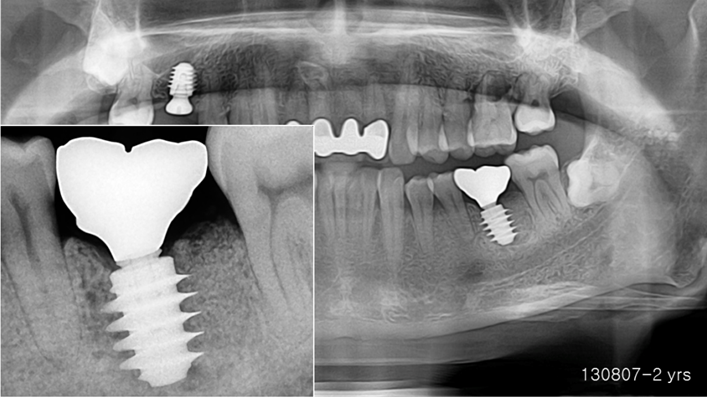

“AnyRidge implant enables fast and stable

osseointegration at this extreme case of bone defect. ”

Clinical case: Bone filling into the bottom of deepest thread at 8.0mm AnyRidge fixture

- Courtesy of Dr. Kwang Bum Park -

Keywords

AnyRidge, Knifethread ,extraction socket, ,initial stability ,Allograft, ,osseointegratio ,Dr. Kwang Bum Park, , Mandibular, Single replacement, AnyRidge, Mega-oss,

Products used

Implant system-AnyRidge, Regeneration-Mega-Oss